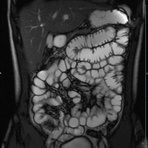

- Dünndarm/Dickdarm

- Chronisch-entzündliche Darmerkrankungen wie Morbus Crohn oder Colitis ulcerosa. Beurteilung der Ausdehnung der Entzündung, Darstellung von Fisteln oder Abszessen bzw. einer Passagebehinderung (MR-Sellink, MR-Kolonographie, beide Untersuchungen nach spezieller Vorbereitung)

- Darstellung bzw. Kontrolle im Verlauf bei perianalen Fisteln und Abszessen

- Verlaufskontrolle des Lokalbefundes nach Rektumentfernung bei Karzinom